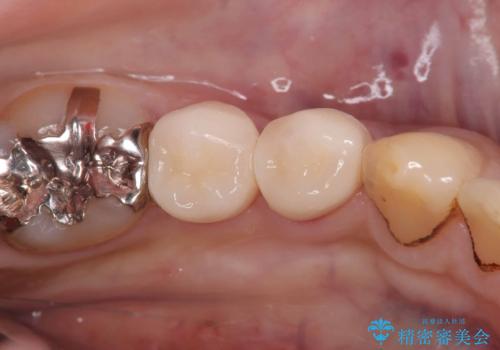

CRの劣化による虫歯|虫歯治療|セラミッククラウン|審美回復|神経を残す治療

担当医 河野豊嘉